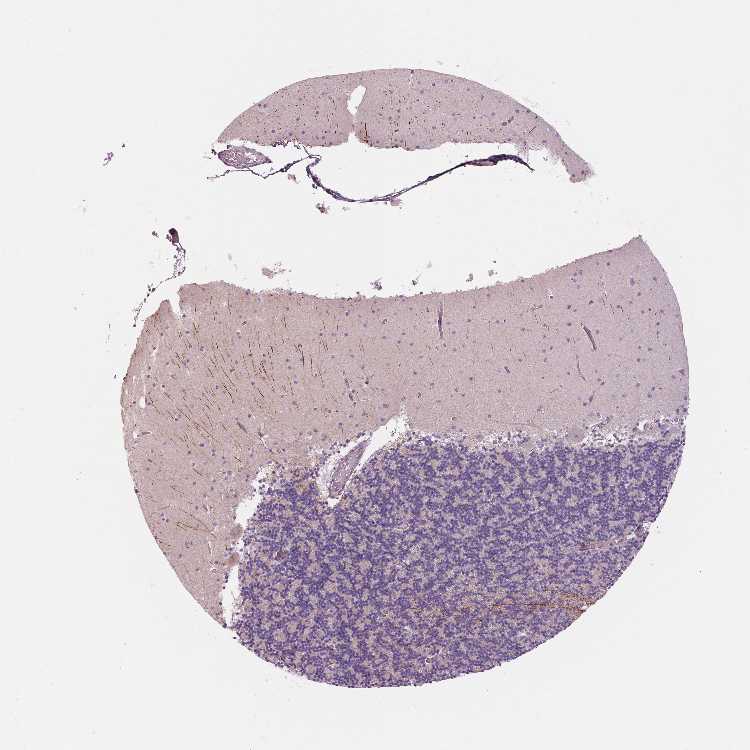

BRAIN CEREBELLUM Show tissue menu

CEREBELLUM - Antibody stainingi

Antibody staining in the annotated cell types in the current human tissue is reported as not detected, low, medium, or high, based on conventional immunohistochemistry profiling in selected tissues. This score is based on the combination of the staining intensity and fraction of stained cells.

Each image is clickable and will lead to virtual microscopy that enables deeper exploration of all samples and also displays staining intensity scores, fraction scores and subcellular localization as well as patient and tissue information for each sample.

Antibody HPA040454

Processes in granular layer High

Processes in molecular layer High

Processes in white matter High